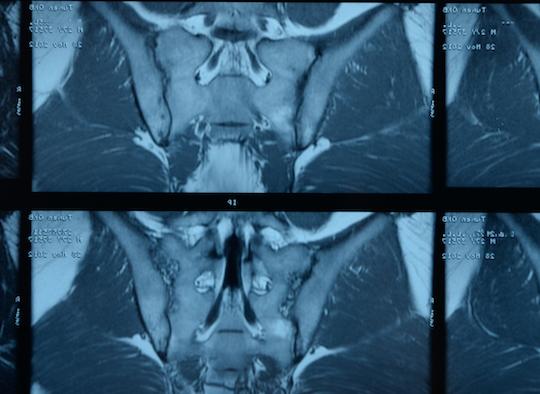

L'âge moyen des malades recrutés est de 37,9(11,0) ans avec une durée de la maladie de 3,7(6,2) ans et 51,2% sont des hommes. Une lésion radiographique des articulations sacro-iliaques, une sacro-iliite en IRM et un HLA-B27 positif ont été observés chez 46,9%, 81,9% et 75,0% des patients respectivement. L'ASDAS moyen à l'inclusion était de 3,0 (± 0,7) et l'ASAS-HI moyenne de 8,6 (± 3,7). Soixante-douze malades par groupe ont participé à la visite d'un an.